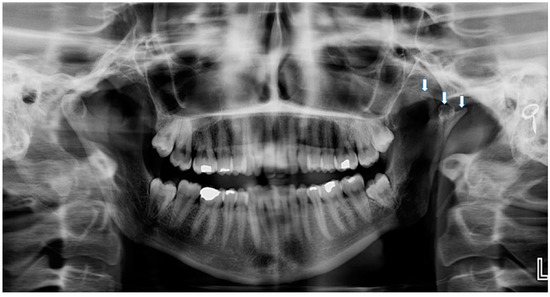

Trifid Mandibular Condyle: Case Report and Current Review of the Literature

2. Case Report